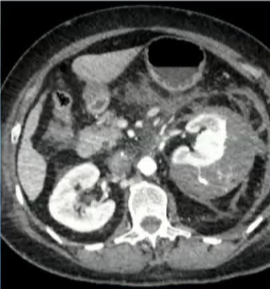

A. CT显示IVC(白色箭头)中血栓的近端范围, |

B. 右下肢浅表水肿(虚线箭头) |